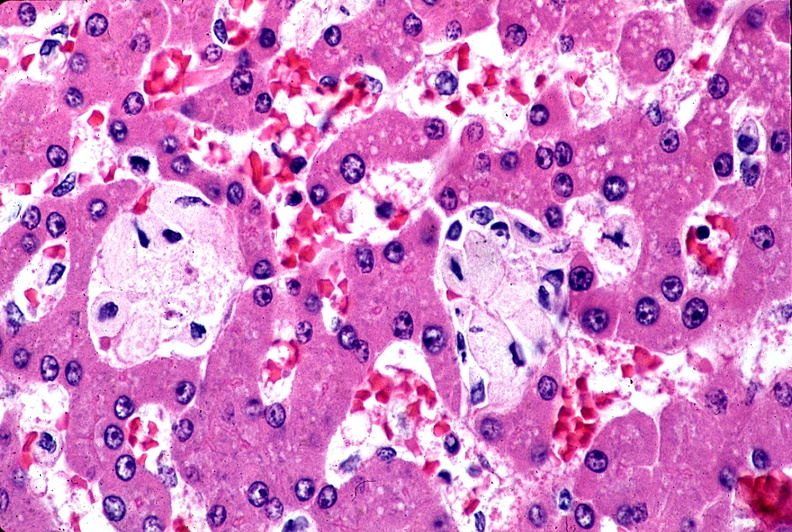

Gaucherova choroba (anglicky Gaucher's disease) je najčastejšou chorobou zo skupiny "netradičných" ochorení. Má tri typy (1, 2, 3) a dve formy. Dedí sa autozomálne recesívne, najviac rozšírená je u židov. Príčinou tohto dedičného ochorenia je znížená aktivita alebo deficit enzýmu beta-glukocerebrozidázy, ktorý je zodpovedný za štiepenie glukozylceramidu z rozpadajúcich sa bunkových membrán. Túto nerozštiepenú látku nevie ľudský organizmus spracovať. Preto ju hromadí v rôznych tkanivách a to predovšetkým v pečeni, slezine a kostnej dreni, zriedkavo aj v nervovom systéme, vrátane mozgu. Túto chorobu prvýkrát opísal francúzsky lekár Phillipe Gaucher v roku 1882. Ochorenie postihuje celosvetovo približne 30 000 ľudí.